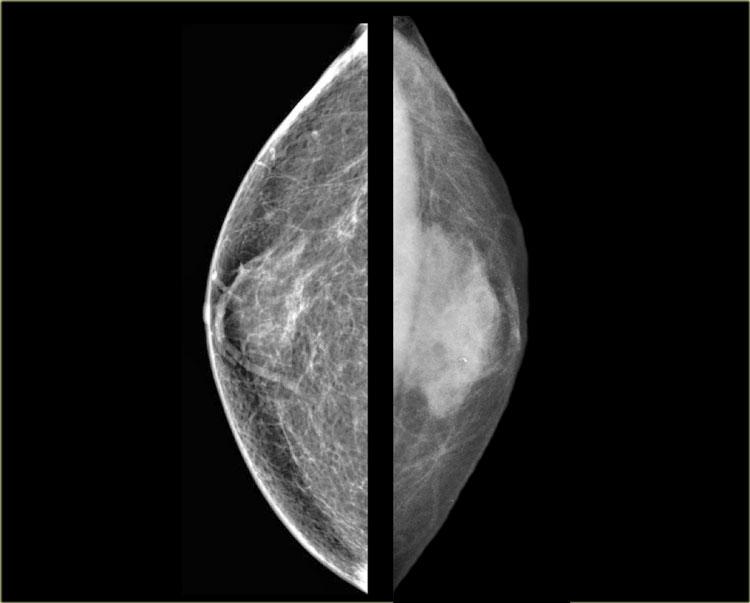

Bên trái là hai trường hợp minh họa cho thấy việc phân biệt vú nam to với ung thư biểu mô trên nhũ ảnh có thể rất khó khăn.

Ung thư biểu mô ở bên phải có bờ được bao bọc rõ hơn một chút so với vú nam to ở bên phải.

Trong chưa đến 10% các trường hợp, cần sinh thiết để phân biệt hai thực thể này.

Bên trái là thêm hai trường hợp nữa.

Ở ngoài cùng bên trái là hình ảnh vú nam to lan tỏa.

Bên phải là một khối ung thư lớn có bờ được bao bọc.

Các trường hợp cuối cùng ở bên trái trông rất giống nhau.

Dựa trên nhũ ảnh, không thể phân biệt được hai trường hợp này.

Trong những tình huống hiếm gặp như vậy, cần phải tiến hành sinh thiết.